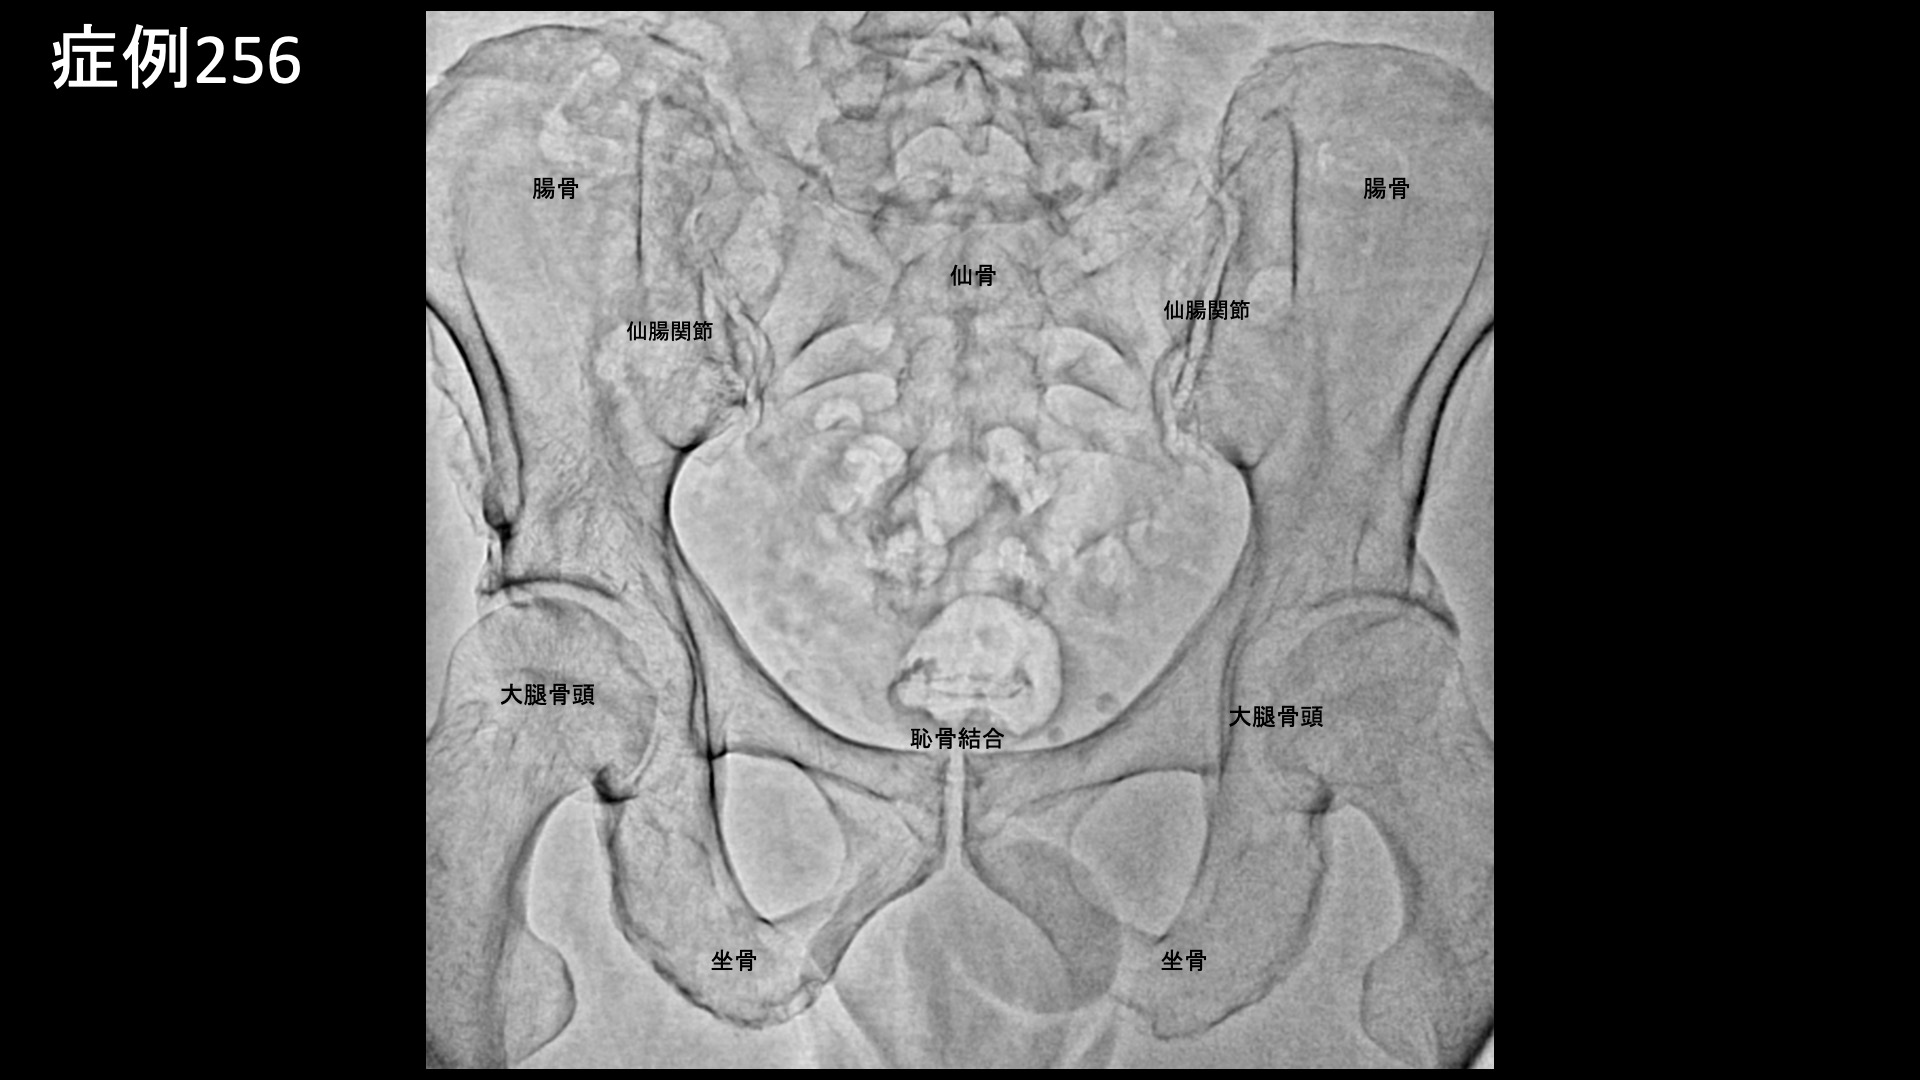

腰:椎間関節炎など 【60代:男性】15年前からの慢性腰痛が急激に悪化して夜も寝られず・・ヘルニアは悪さをしていないなら原因は?(筋・筋膜性疼痛症候群、仙腸関節障害、腰椎椎間板ヘルニア) 2025.12.23 鴨井院長による動画解説 受診までの経過 15年前から慢性的に腰痛がありました。1年前にひどい痛みと脱力に襲われ、MRI検査を受けたところ、腰椎椎間板ヘルニアと診断されました。手術も検討していましたが、自然軽快し、再び歩けるようになりました。しかしながら、右側の腰痛は軽快したものの、左側の強い腰痛が残っていました。ヘルニアで強く圧迫されていたのは右側の神経であったため、整形外科では首を傾げられました。じっとしていると増悪し、長時間の立位でも増悪しました。そのため、夜痛みで寝られないことが多く、起床後も11時くらいになってようやく動けるようになる状態でした。 *50年前に腸骨骨折の既往あり 診察時の所見 MRI検査を確認すると、やはりヘルニアで圧迫を受けているのは右側であり、ヘルニア所見と症状は合致しませんでした。腰の可動域をチェックすると。すべてに動作において中等度の制限がありました。股関節の内外旋動作では可動域は保たれているものの、動きに抵抗があり比較的高度の硬さがありました。触診では、第2―4腰椎レベルでは左腰部の筋肉部において有意に圧痛が認められました。レントゲンでは、左上前腸骨棘を中心に腸骨に骨表層不整像や骨硬化像が見られており、同部位に付着する腸骨筋、縫工筋、大腿筋膜張筋が関与する筋・筋膜性の障害が示唆されました。いずれも股関節の動きに関与する筋肉です。腸骨にはほかに腸腰筋や臀筋が関与し、いずれも腰臀部痛の原因として重要です。こうした腸骨の変化や、筋硬直、その他の特徴的な身体所見から総合的に判断して、筋・筋膜性疼痛症候群を主体として、仙腸関節障害も合併している状態と判断しました。骨盤の不安定性が一因ですので、腸骨骨折の既往とも関係があるかもしれません。以上より治療適応と判断し、モヤモヤ血管(病的新生血管)に対する運動器カテーテル治療(微細動脈塞栓術)を受けていただきました。 治療の所見 第2腰動脈~第4腰動脈の筋肉枝を選択的に治療し、さらに、腰痛の主要責任血管の一つである腸腰動脈や外側仙骨動脈、臀筋群に関与する上殿動脈、下殿動脈、股関節の動きにも関わる閉鎖動脈やその他の筋肉枝など複数個所の治療を広範囲に行いました。 治療後の経過 治療後2週間、まだ大きな変化はないものの、痛みが少しましになったほか、寝られる日が多くなってきました(以前は痛みで寝られないことが多かった)。治療後1ヶ月半、時々痛むことはあるものの、だいぶ良くなってきました。痛みで寝られないということは無くなりました。『本当に寝られなくて辛かったので嬉しい、何十歳か若返ったように思う』と大変喜ばれました。まだ左腰部に1か所だけ、塊のように感じる部分が残っているものの、それもだいぶ柔らかくなりました。治療後3ヶ月、塊の部分はやはり一定の違和感があるものの、痛みは感じなくなりました。全体的には疲れると疼くように痛むことがあるものの、元の7割程度の痛みは解消されました(3/10程度に改善)。夜寝られないほどの腰痛というのはかなり重症度が高いわけですが、これほどの状態であっても、MRIで原因がわからないことは珍しくありません。丹念に診察をして原因を見つけ出し、治療を行うのが痛み治療専門医師の腕の見せ所ですが、良い結果が得られて本当に良かったです。残存症状については追加カテーテル治療が有効ですが、生活習慣の改善や運動療法を地道に行っていくことでさらなる緩和が期待できます。引き続きしっかりとサポートしていきたいと思います。 本症例では、とにかく体の硬さや筋硬直が根底にありました。こうした状態では、腰痛はほぼ必発です。骨格のほか、運動不足や、過剰なトレーニング、急激な体重変動、加齢などが原因です。懸念のある方は、発症予防、再発予防のために硬さの解消に取り組んでください。原因により対処方法は異なりますが、日常的に軽めの運動を取り入れることはいずれの場合も有効です。 筋・筋膜性疼痛症候群の詳細はこちら 【70代:男性】頭痛、こめかみ・眉上の痛み、耳鳴り~頭部顔面の帯状疱疹後遺症に対するモヤモヤ血管治療(帯状疱疹後遺症) 前の記事 【50代:女性】8年前からの両膝・両足首の痛みに加えて踵まで痛み平地歩行もままならず・・進行性の変形性膝関節症および足関節症、足底筋膜炎の合併例に対して2回の運動器カテーテル治療を行った症例(変形性膝関節症、変形性足関節症、足底筋膜炎、肥満) 次の記事